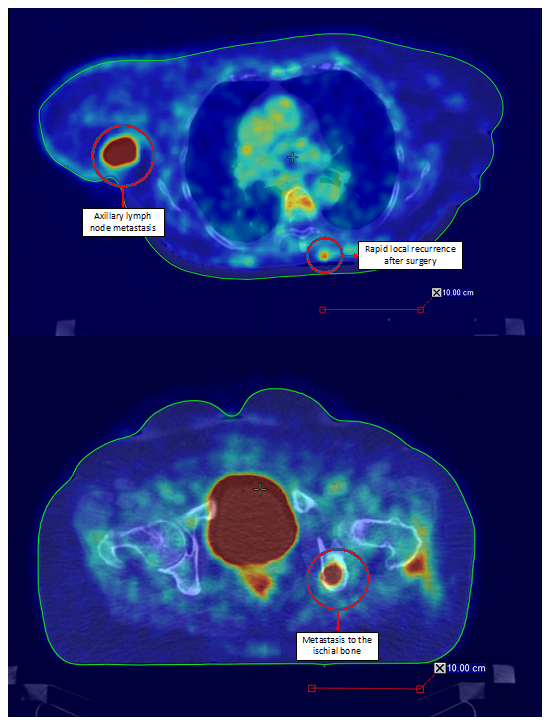

- Sachpekidis, C.; Sidiropoulou, P.; Hassel, J.C.; Drakoulis, N.; Dimitrakopoulou-Strauss, A. Positron Emission Tomography in Merkel Cell Carcinoma. Cancers 2020, 12, 2897. [Google Scholar] [CrossRef]